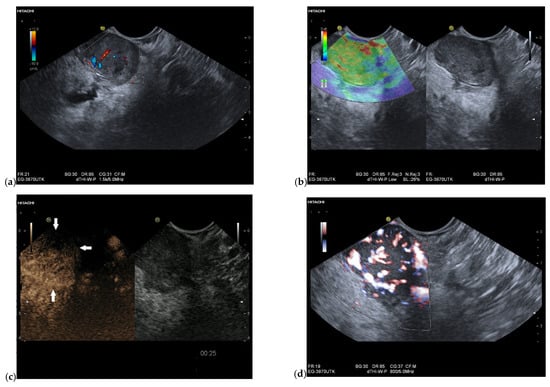

3.4. CEUS and CH-EUS

| Colour Doppler Imaging | RCC metastases are hypervascularized Most other pancreatic metastases are hypovascularized | No hypervascularization | Hypervascularized |

| Cases | CEUS | CH-EUS | ||

|---|---|---|---|---|

| Arterial Phase | Venous Phase | Arterial Phase | Venous Phase | |

| RCC metastases [83] (n = 4) | Hyperenhancement, Early | Hyperenhancement | ||

| RCC metastases [61] (n = 3) | Hyperenhancement, homogeneous pattern | Slow washout | ||

| RCC metastasis [86] (n = 1) | Hyperenhancement, Inhomogeneous pattern | No washout | ||

| Melanoma metastasis [63] (n = 1) | Iso- to slightly hypoenhanced | Hypoenhanced | ||

| Melanoma metastasis [87] (n = 1) | Isoenhanced | Hypoenhancement of the peripheral rim, central non-enhancement | ||

| Melanoma metastasis [61] (n = 1) | Isoenhanced, heterogeneous | Fast washout | ||

| SCLC metastasis [83] (n = 1) | Hyperenhancement | Rapid washout | ||

| Breast, ovarian, colon metastases, sarcoma metastases [61] (n = 6) | Hypoenhancement, homogeneous or heterogeneous | Fast or slow washout | ||

| Lymphoma metastasis [61] (n = 1) | Hyperenhancement, homogeneous pattern | Fast washout |